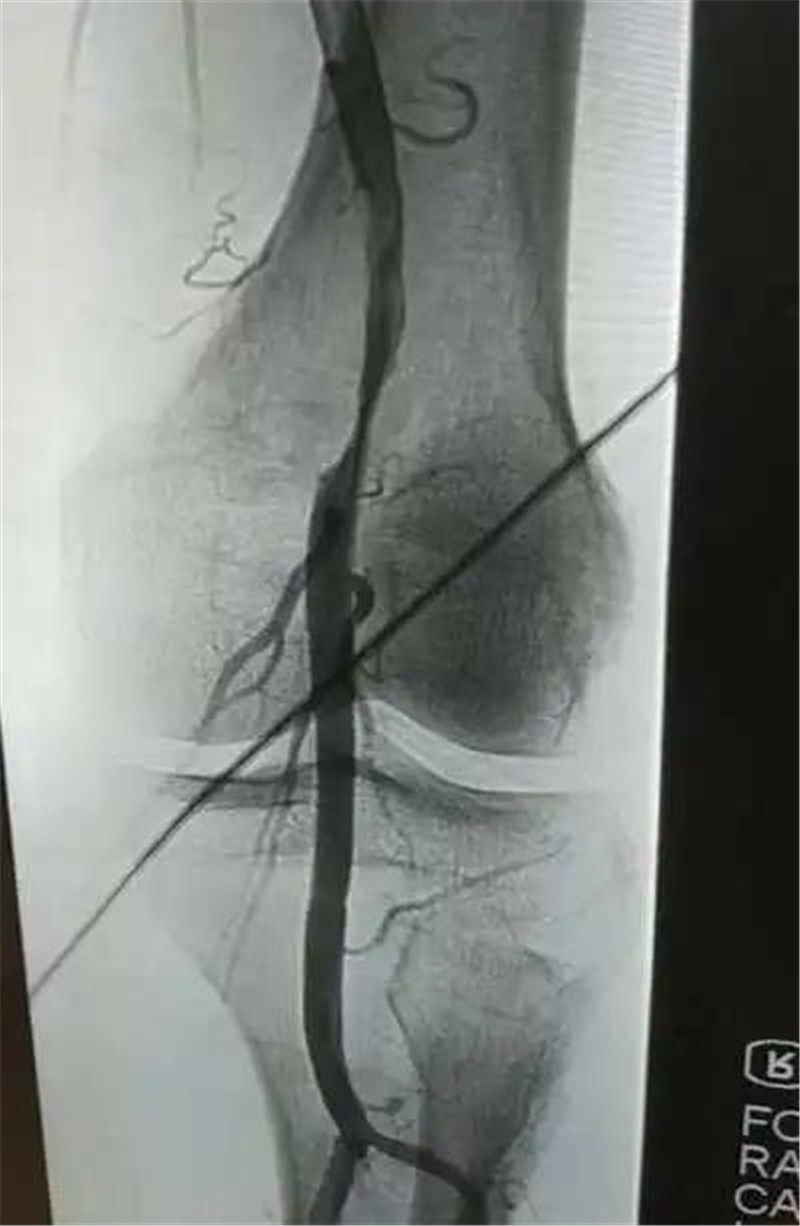

近日,43岁的邓先生因右下肢疼痛伴肢体发凉、麻木,运动时加重,半天后急诊入住三水区人民医院,内分泌科为其安排了右下肢动脉造影+球囊扩张术,术后恢复良好,邓先生于11日上午出院。“刚做完手术,脚底就转暖了,整个下肢也不痛了,效果很明显。”邓先...